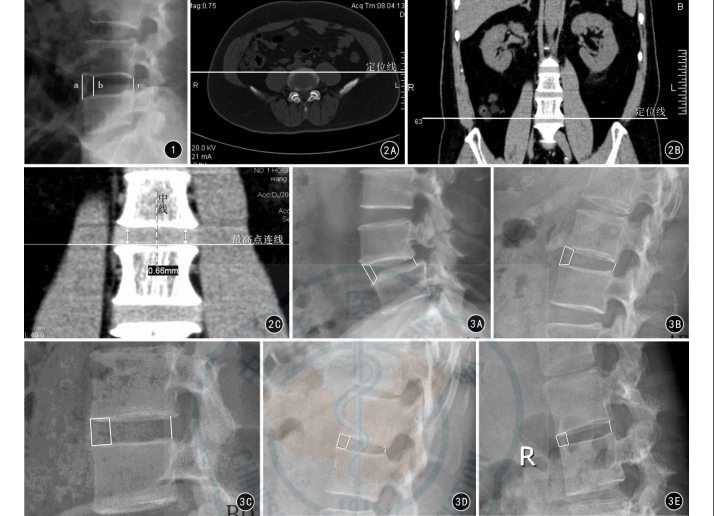

1.3 测量方法

依据椎间隙盘状小凹将腰椎间隙分为前纤维环部、Disc Pit和后纤维环部3个部分。使用Philips Dicom Viewer软件对术前的209个病变椎间隙的X线影像进行测量,测量项目包括椎间隙前缘高度(a)、椎间隙盘状小凹前端高度(b)、椎间隙后缘高度(c)。见图1。使用Philips Dicom Viewer软件对术前的209个病变椎间隙CT影像的椎间隙盘状小凹前端中心处与两侧的高度差值进行测量。见图2。

1.4分型标准

依据上述测量指标进行分型。(1)AD型:a/b>1且c/b>0.5;(2)AE型:a/b>1且c/b≤0.5;(3)BD型:a/b=1且c/b>0.5;(4)BE型:a/b=1且c/b≤0.5;(5)CD型:a/b<1且c/b>0.5;(6)CE型:a/b<1且c/b≤0.5。见图3。

图1 腰椎失稳症患者侧位X线影像测量腰推间隙参数 a:椎间隙前缘高度,为相邻两椎体前缘点间的直线距离; b:椎间隙盘状小凹前端高度,为椎间隙盘状小凹两前缘点间的直线距离;c:椎间隙后缘高度,为相邻椎体两后缘点间直线距离 图2 测量方法 2A 将Philips Dicom Viewer软件的定位线工具定位于椎体横断面CT影像 2B 与2A相对应的椎体冠状面CT影像 2C 在椎体冠状面影像上做中心线,取椎体两侧最高点(双头箭)做连线,测量椎体中心线与椎体接触点至椎体两侧最高点连线的垂直距离 图3 腰椎失稳症病变椎间隙X线测量分型 3A AD型 3B AE型 3C BD型 3D BE型 3E CD型